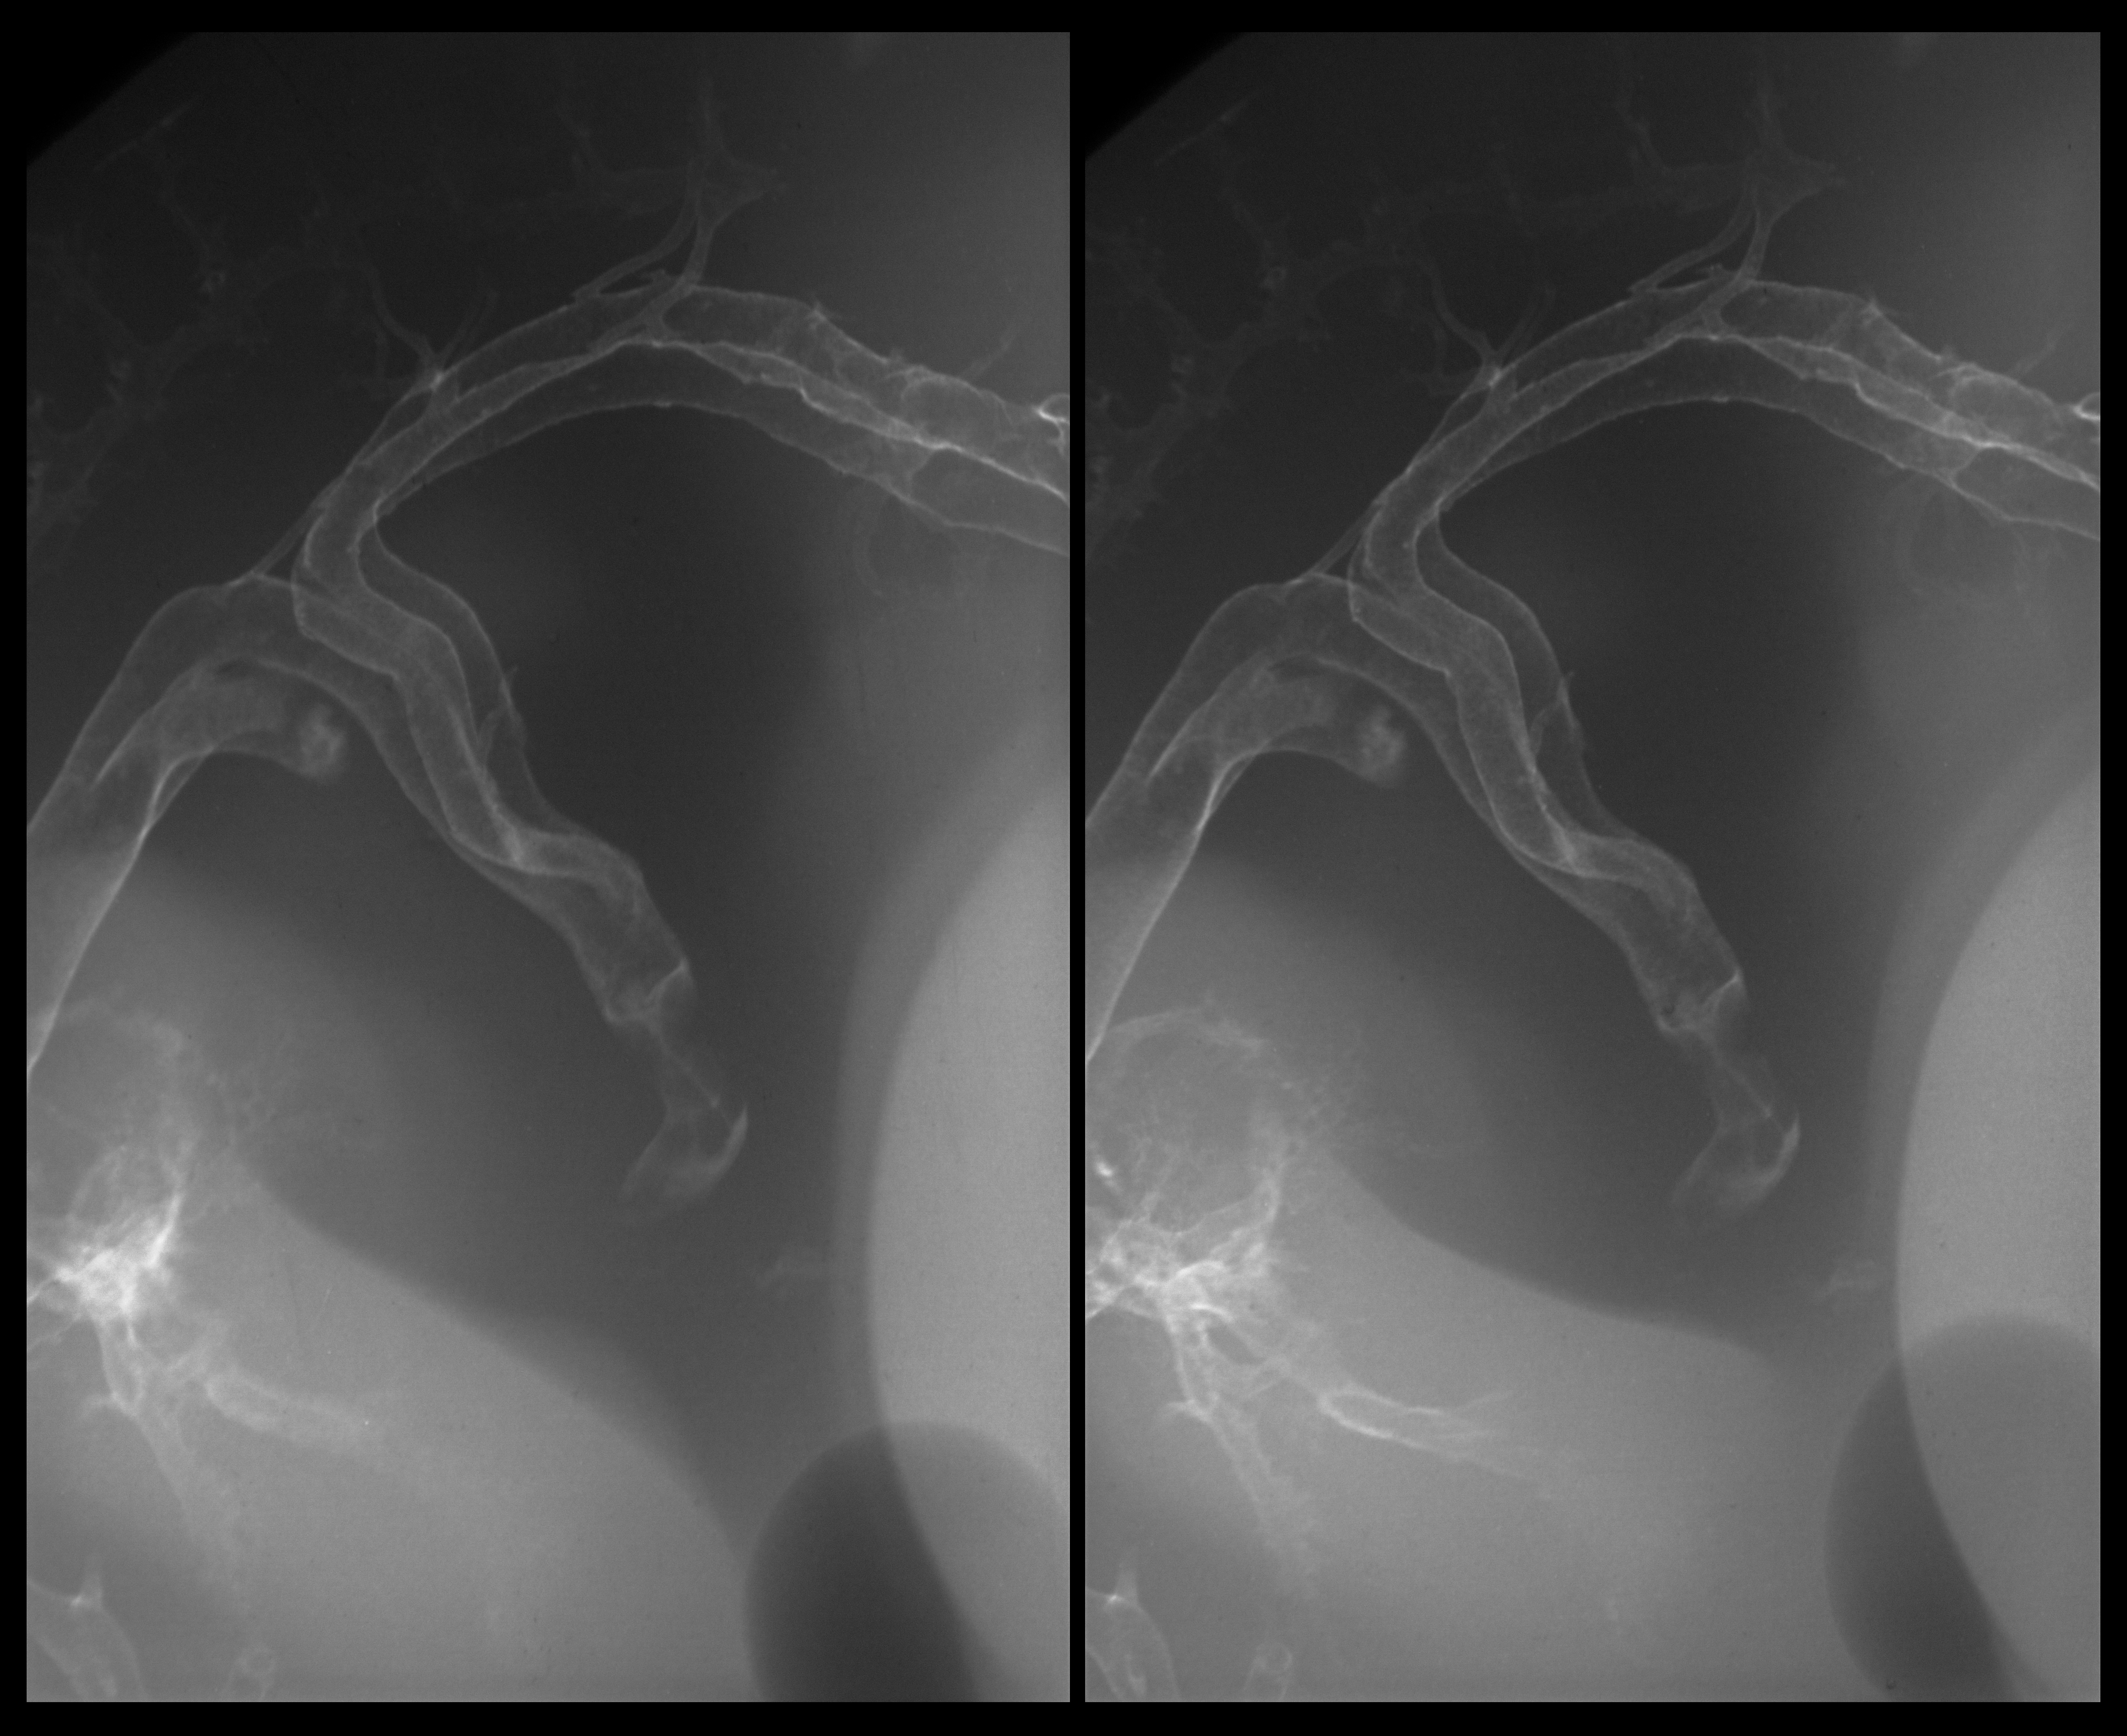

Stereo X-Ray Micrographs